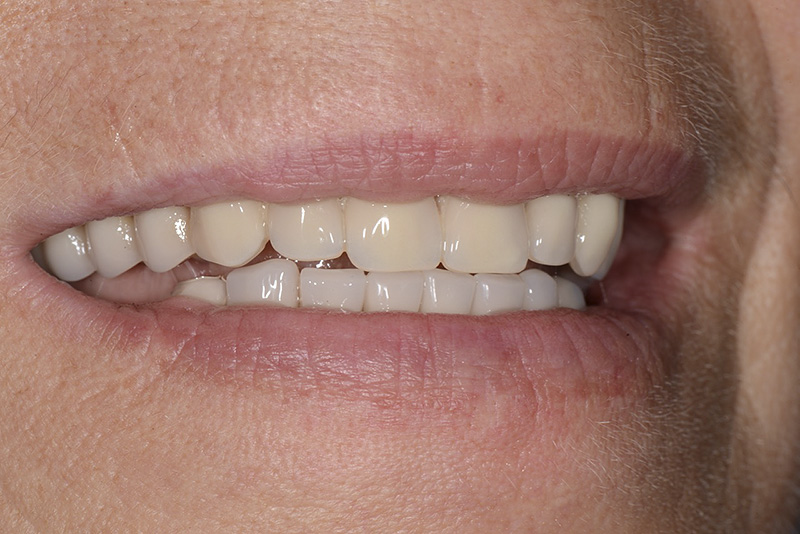

PREMESSA: in seguito all’estrazione dell’incisivo laterale superiore di destra, resasi necessaria per cause batteriche, si decide di affrontare il caso con il posizionamento di un impianto in sostituzione dell’elemento mancante dopo guarigione del sito infetto. Con tecniche rigenerative sia dei tessuti ossei mancanti a causa dell’infezione pregressa, sia dei tessuti gengivali che appaiono inizialmente troppo spostati in alto, si ripristina una corretta morfologia delle parabole (contorni) gengivali e delle papille interdentali (triangoli di gengiva tra due denti vicini).

Vengono utilizzati 2 tipi di provvisori: il primo, cementato ai denti vicini, viene utilizzato dal momento dell’estrazione del dente fino ad impianto osteointegrato (circa 6 mesi); il secondo, avvitato direttamente all’impianto, ha una funzione di prova estetica ma soprattutto di guida per la maturazione dei tessuti gengivali peri-implantari portandoli verso la maturazione completa prima di posizionare la corona finale in disilicato di litio.